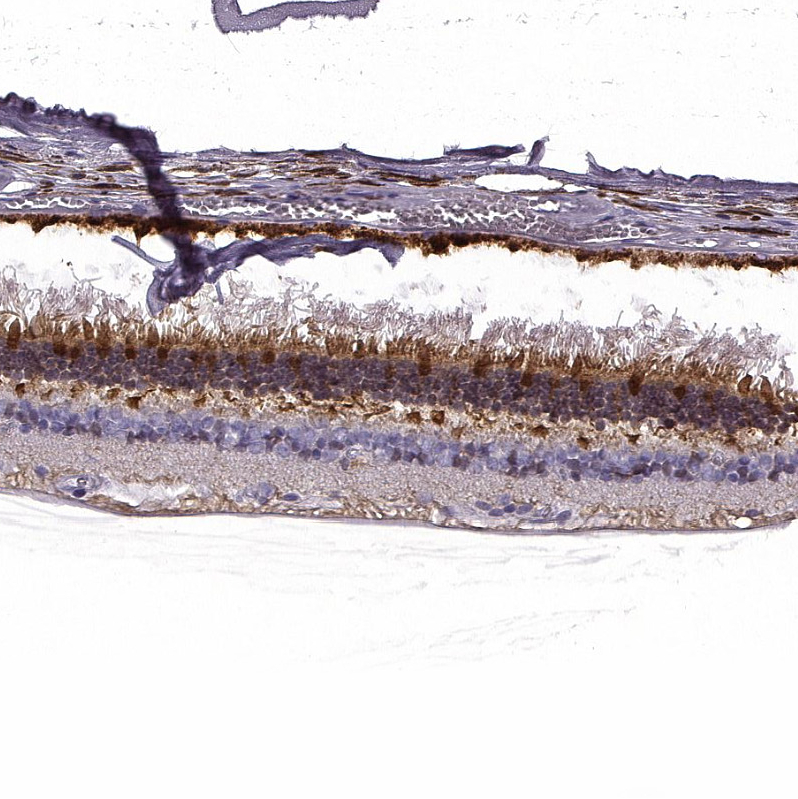

Immunohistochemical staining of human retina shows moderate to strong positivity in photoreceptor layer as well as outer plexiform layer.